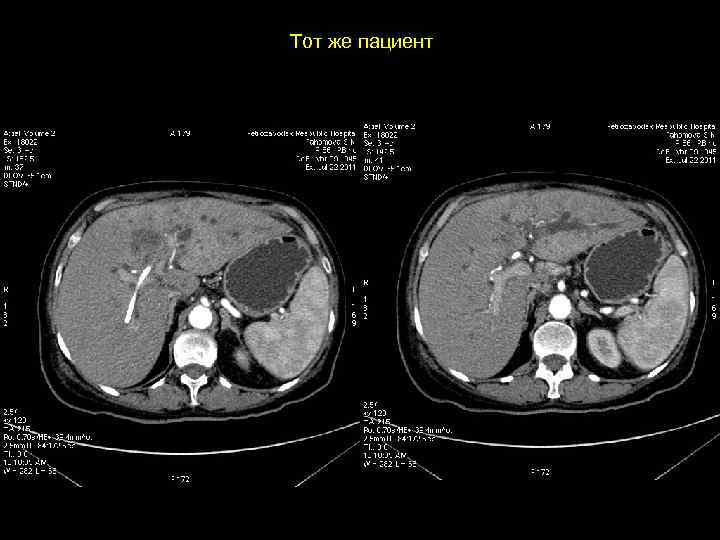

Тот же пациент